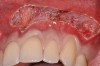

The flap approach follows an incision design where the crest of the papilla is preserved and a V-type incision is made in the papillary tissues (Figure 4). This allows the preexisting papillary tissues in the area just inferior to the contact point of the natural teeth affected to be used as a tissue bed to provide vascularization to the flap/dermis complex. Prior to securing the dermal matrix tissue, the papillary tissues that remain after the incision technique outlined must be de-keratinized by using a #4 round diamond bur. This allows for the introduction of initial blood flow and vascularization of the dermal matrix tissues and nourishment of the coronally repositioned flap in the critical area of the interproximal papillary tissues. After securing the dermal matrix tissue from the palatal/lingual aspect of the teeth being treated and coronally repositioning the buccal flap, closure is achieved using an interrupted sling suturing technique.

After initial incision techniques were done, a papillary-sparing incision was performed, leaving the crest of the papilla intact (Figure 10), thus allowing flap closure to be accomplished with a bed of autogenous tissue to support revascularization of the dermis/buccal flap complex. A full-thickness flap was then elevated to the mucogingival junction, after which a split-thickness dissection with a blunt elevator superior to the mucogingival junction area was performed to allow for release of tension and to let the buccal flap be mobilized coronally at closure (Figure 10). Care must be taken to avoid perforating the tissue in the region of the vestibuloplasty incision. After tension-free release of the flap, root planing of the exposed root surfaces was accomplished, followed by removal of the smear layer of cementum and chemical detoxification with a citric acid solution pH1 applied over the previously root-planed surfaces. After root preparation, the keratinized papillary tissues that remained following initial incisions were de-keratinized by using a #4 round diamond on a high-speed handpiece. De-keratinization provided a wound bed that enabled the dermal matrix graft to be secured and supported revascularization of the coronally repositioned buccal flap at closure.

Fig 10. Initial incisions, and blunt, split-thickness dissection for tension-free closure.

Figure 10